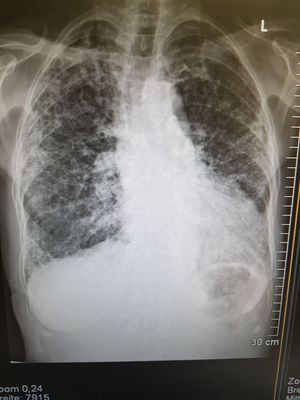

X-ray of 86 year old woman

Fibrosis pulmonar and cardiomegalia (sorry for the quality)

Is this patient suffering from TB ???

No, according to doctors she suffers from fibrosis